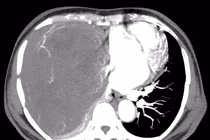

E kíp phẫu thuật đã rất khó khăn, tỉ mỉ bóc tách khối u hiếm gặp, lớn chiếm gần hết khoang lồng ngực, lại có nhiều mạch tân tạo... U xơ đơn độc màng phổi lành tính thường có tiên lượng tốt sau phẫu thuật nên cần điều trị sớm.